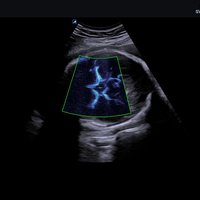

Das X-CUBE 70 fügt sich nahtlos in die neue X-CUBE Serie ein. Wie bereits das X-CUBE 90 so nutzt auch das X-CUBE 70 Farbdopplersystem die Bildverarbeitungstechnologien eines Premiumsystems, eine Vielzahl neuer Breitband-Schallköpfe mit X+ Crystal SignatureTM Technologie und neuen technischen Raffinessen.

Das X-CUBE 70 bietet modernste Technologien für eine objektive und akkurate Diagnose. Intelligente klinische Module heben das System auf ein neues diagnostisches Niveau. Es erweitert Ihre Fähigkeiten und die Bandbreite Ihrer Möglichkeiten. Dazu gehören Module wie MicroView, point Shear Wave Elastographie (pSWE), oder auch die Kontrastmittelsonographie.

• SVC1-8H (1-8 MHz) für Ultraschalluntersuchungen in Bereichen Abdomen, Geburtshilfe, Gynäkologie, Urologie, Pädiatrie, EM